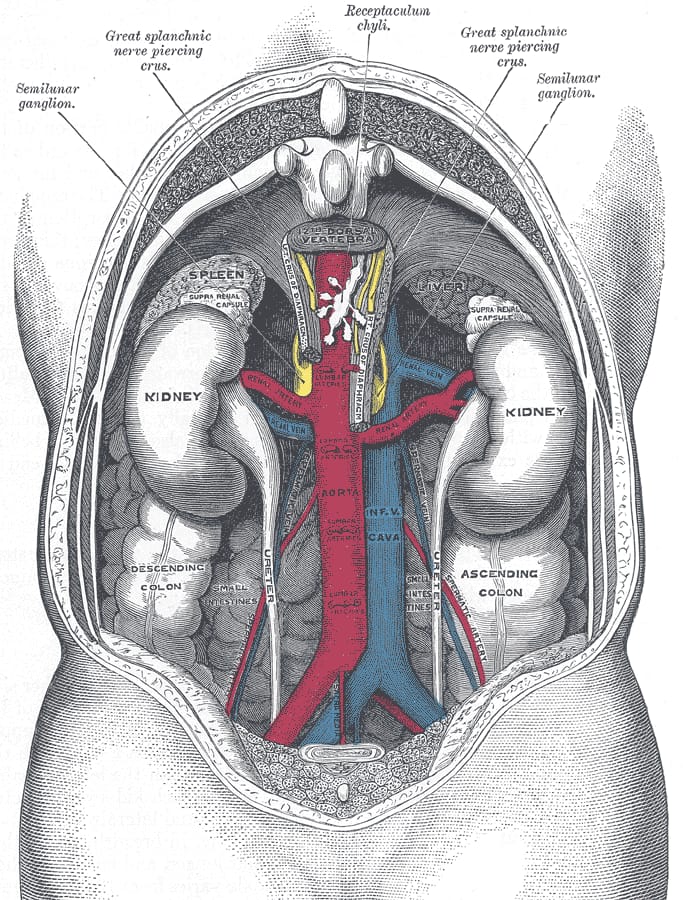

Kidneys

Credit: Henry Vandyke Carter · Public domain

The kidneys are a pair of organs that clean your blood. They sit in the back of your belly, one on each side of your spine, just below your ribs. Each kidney is shaped like a large bean and is about the size of your fist. Together, the two kidneys do one of the most important jobs in the body. They take out waste and extra water and turn it into urine.

Blood flows through your kidneys all day and all night. About every minute, half a cup of blood enters each kidney. The kidneys pull out things the body does not need, like leftover salts and a waste product called urea. They also save things the body does need, like water and sugar, and send them back into the blood. The waste leaves the kidneys as urine, which travels down two tubes called ureters and is stored in the bladder.

Kidneys do more than make urine. They also help keep your blood pressure steady, tell your bones to stay strong, and signal the body to make more red blood cells when you need them. They check the amount of water in your blood every few seconds. If you drink a big glass of water, your kidneys notice within minutes and start making more urine. If you forget to drink water on a hot day, they hold water back so you do not dry out.